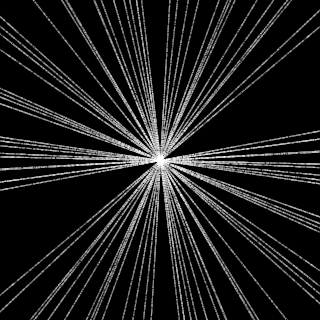

This article presents a novel undersampled magnetic resonance imaging (MRI) technique that leverages the concept of Neural Radiance Field (NeRF). With radial undersampling, the corresponding imaging problem can be reformulated into an image modeling task from sparse-view rendered data; therefore, a high dimensional MR image is obtainable from undersampled $k$-space data by taking advantage of implicit neural representation. A multi-layer perceptron, which is designed to output an image intensity from a spatial coordinate, learns the MR physics-driven rendering relation between given measurement data and desired image. Effective undersampling strategies for high-quality neural representation are investigated. The proposed method serves two benefits: (i) The learning is based fully on single undersampled $k$-space data, not a bunch of measured data and target image sets. It can be used potentially for diagnostic MR imaging, such as fetal MRI, where data acquisition is relatively rare or limited against diversity of clinical images while undersampled reconstruction is highly demanded. (ii) A reconstructed MR image is a scan-specific representation highly adaptive to the given $k$-space measurement. Numerous experiments validate the feasibility and capability of the proposed approach.